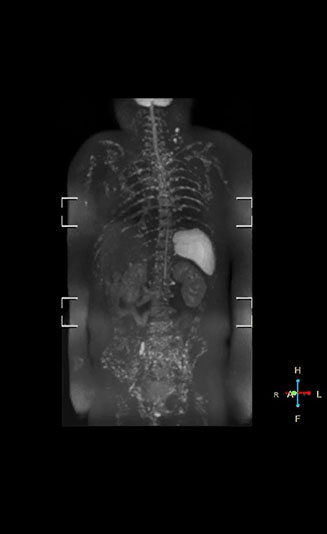

“Switching to coronal DWIBS – rather than axial – further shortens scan time,” says Mr. Naka. “Important is that a dS SENSE factor of 5 shortens exam time while high image quality can be maintained, thanks to Ingenia’s dStream architecture.” He adds that the coronal orientation also avoids artifacts that are specific to combining axial images.

“When we use a coronal DWIBS acquisition, we can perform a full whole body examination, including other required sequences, within 30 minutes,” he says.

Dr. Nobusawa notes that acceptance of whole body DWI accelerated after the hospital installed the Ingenia 1.5T which allowed them to optimize the protocol to their needs. “The Philips system helped us promote the technique, because the DWIBS image quality was so high with Ingenia. It provides high quality in the coronal images, and a short acquisition time plus high SNR thanks to the dStream technology,” he says.